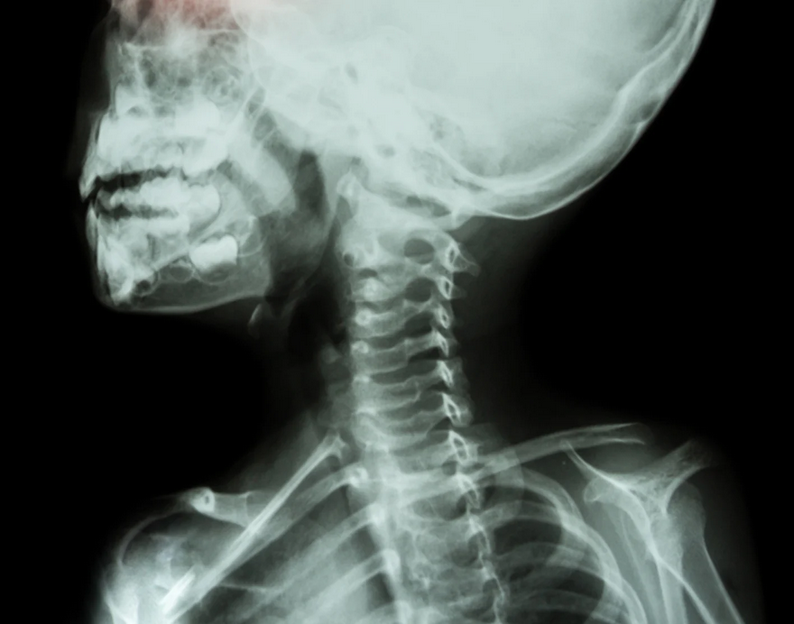

به گزارش خبرگزاری علم و فناوری آنا،اشعه ایکس در جهان امروز نقش کلیدی در بسیاری حوزهها دارد. برای مبارزه با بیماریهای عفونی مهلک، باید ارگانیسمهایی مسبب بروز آنها را بشناسیم؛ برای طراحی نسل بعدی خودروهای برقی، باید باتریهای بهتر و بادوامتری برای تامین انرژی آنها بسازیم و برای ساخت موتورهای کارآمدتر و ایمن تر برای هواپیماها، به مواد قوی تر و بادوام تری نیاز داریم. برای انجام همه این کارها به یک منبع نور پرتو ایکس قدرتمند نیاز است. پرتوهای ایکس گرچه نور هستند، اما مرئی نیستند. ممکن است با دستگاههای اشعه ایکس که دندانپزشکان برای عکس گرفتن از داخل دندانها استفاده میکنند آشنا باشید. منبع نوری مانند «منبع فوتون پیشرفته» (APS)، یکی از تاسیسات کاربری دفتر علوم وزارت انرژی آمریکا در آزمایشگاه ملی آرگون، نور پرتو ایکس مشابهی را تولید میکند، اما یک میلیارد برابر درخشان تر است.

با نوری به این درخشانی چه میتوان کرد؟ APS مانند یک میکروسکوپ غول پیکر عمل میکند، اما برخلاف نور مرئی، اشعه ایکس به درون مواد نفوذ میکند و به دانشمندان در دیدن عمق آنها یاری میرساند. پرتوهای اشعه ایکس را میتوان به قدری متمرکز کرد که مثلا دانشمندان میتوانند با استفاده از این اشعه آنچه در داخل باتری در حین استفاده اتفاق میافتد را «ببینند» و در نتیجه بتوانند باتریهای کم مصرف تری را توسعه دهند.